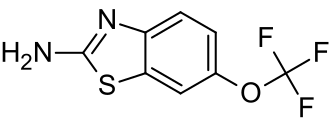

Medications

Disease-slowing treatments

Riluzole has been found to modestly prolong survival by about 2–3 months.[107][106] It may have a greater survival benefit for those with bulbar-onset ALS.[106] It may work by decreasing release of the excitatory neurotransmitter glutamate from pre-synaptic neurons.[10] The most common side effects are nausea and a lack of energy (asthenia).[106] People with ALS should begin treatment with riluzole as soon as possible following their diagnosis.[105] Riluzole is available as a tablet, liquid, or dissolvable oral film.[15]

Edaravone has been shown to modestly slow the decline in function in a small group of people with early-stage ALS.[108][109] It may work by protecting motor neurons from oxidative stress.[110] The most common side effects are bruising and gait disturbance.[109] Edaravone is available as an intravenous infusion or as an oral suspension.[111]

AMX0035 (Relyvrio) is a combination of sodium phenylbutyrate and taurursodiol, which was initially shown to prolong the survival of patients by an average of six months.[112] Relyvrio was withdrawn by the manufacturer in April 2024[113] following the completion of the Phase 3 PHOENIX trial[114] which did not show substantial benefit to ALS patients.

Tofersen (Qalsody) is an antisense oligonucleotide that was approved for medical use in the United States in April 2023, for the treatment of SOD1-associated ALS.[115] In a study of 108 patients with SOD1-associated ALS there was a non-significant trend towards a slowing of progression, as well as a significant reduction in neurofilament light chain,[116] a putative ALS biomarker thought to indicate neuronal damage.[117] A follow-up study and open-label extension suggested that earlier treatment initiation had a beneficial effect on slowing disease progression. Tofersen is available as an intrathecal injection into the lumbar cistern at the base of the spine.[115]

A 2025 phase II study published found that tetramethylpyrazine nitrone is safe for patients with ALS, but it did not show a significant advantage over placebo in the primary efficacy measure.[118] Researchers noted that the drug may help slow the decline in grip strength, however further clinical trials are necessary to confirm its potential benefits.[119]

Symptomatic treatments

Other medications may be used to help reduce fatigue, ease muscle cramps, control spasticity, and reduce excess saliva and phlegm.[102] Gabapentin, pregabalin, and tricyclic antidepressants (e.g., amitriptyline) can be used for neuropathic pain, while nonsteroidal anti-inflammatory drugs (NSAIDs), acetaminophen, and opioids can be used for nociceptive pain.[36]